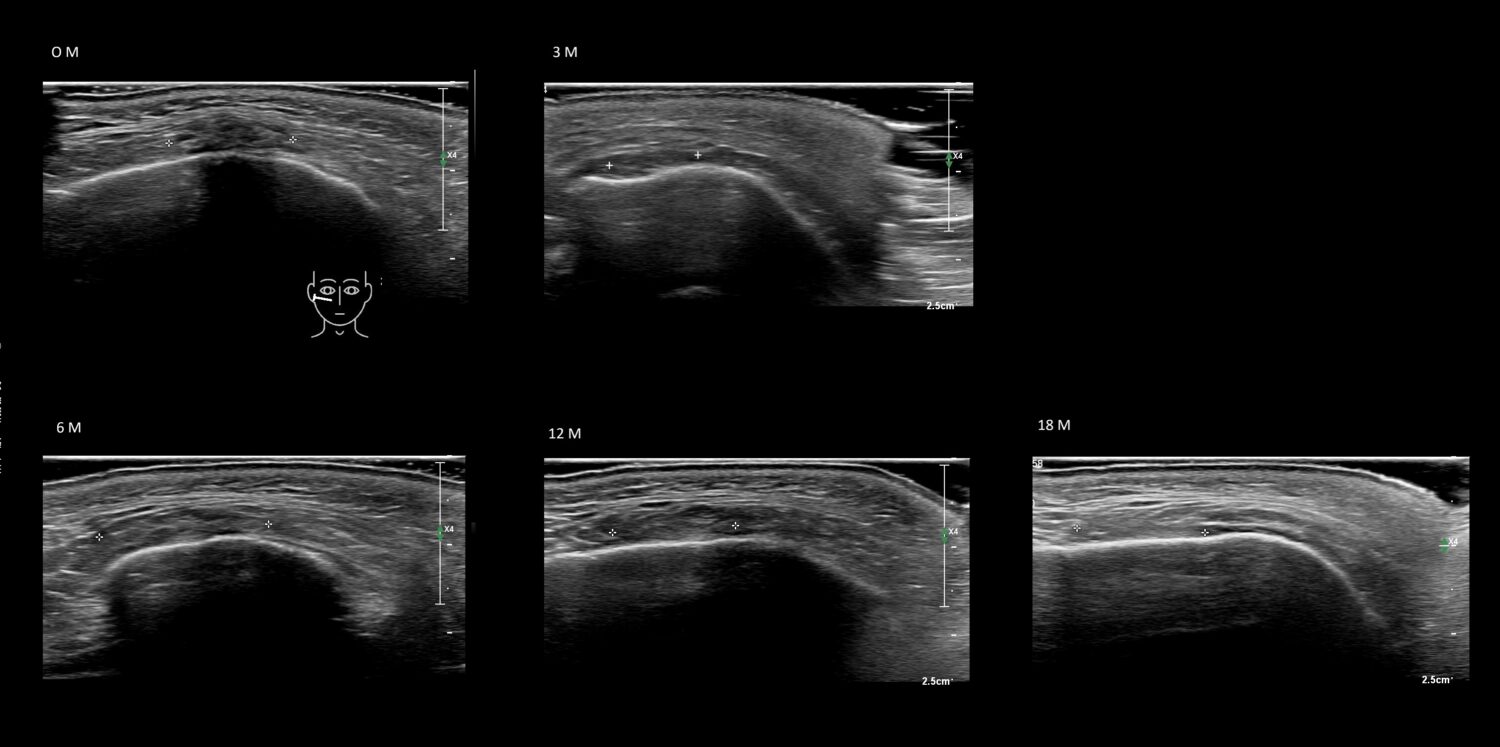

Fillers

Draw in the image on the right where the fillers are located. To check if your answer is correct, please click on the secondary image.

Fillers

Draw in the second image below where the fillers are located. To check if your answer is correct, swipe the first image to the right.